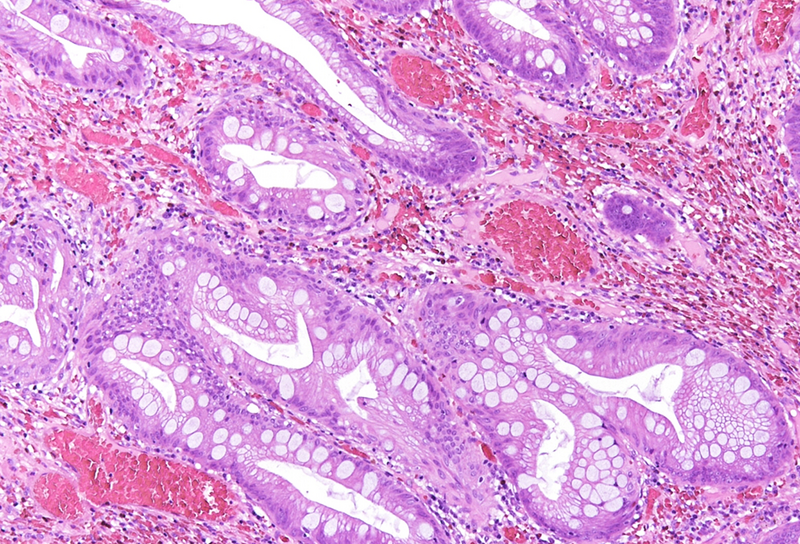

Histologically, the lesion exhibited a complex lobulated architecture (Panel A), with central cores of ramifying bands of smooth muscle extending from the muscularis mucosae into the lamina propria, configuring an arborizing pattern (Panel B). The epithelium exhibited neither cytologic nor architectural atypia and was regarded as reactive (non-dysplastic), with some glands showing dilation and distortion (Panel C). Recovering epithelium was observed on the surface, together with granulation tissue (Panel D).